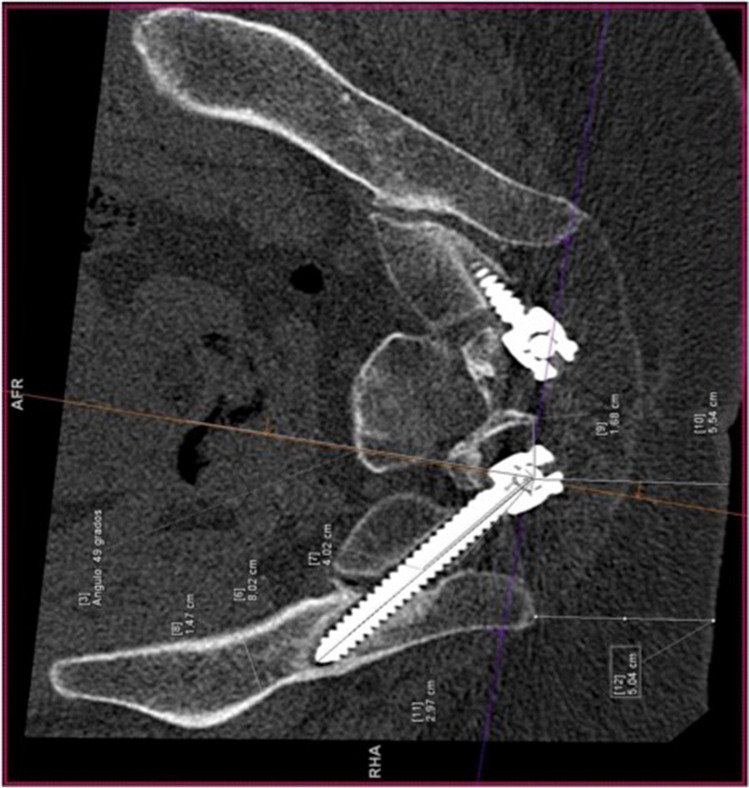

CT was rotated, until the screw holes on each side were observed in order to measure the different radiological parameters. To obtain the ideal trajectory on each patient [11], CT imaging planes were rotated until the viewing angle was perpendicular to the wing of the ilium. In this position, the projection of the line between the PSIS and the anterior inferior iliac spine (AIIS) is the longest and most horizontal, hence matching the greatest length and width of osseous channel. We draw a line perpendicular to the narrowest region, and the ideal entry point was obtained (Fig. 2).

Fig. 2.

Ideal trajectory. CT imaging plane (projection of the line between PSIS and the anterior inferior iliac spine (AIIS)). The ideal trajectory is the line drawn perpendicular to the narrowest region

Then the measurements were determined as follows [19]:

Sag angle: in the sagittal plane, defined as the angulation in the caudal trajectory.

Tsv angle: in the transverse plane, defined as the angulation in the lateral trajectory.

Max-length: defined as the maximal distance in a trajectory from S2 ala to the AIIS.

Sacral distance: defined as intrasacral trajectory length.

Iliac width: in the transverse plane, defined as the narrowest iliac width measured between the inner cortices.

S2 midline: defined as the distance of the starting point lateral from the middle line of S2.

Skin distance: defined as the distance of the starting point lateral from the skin.

Iliac wing: defined as the distance of the starting point lateral from the nearest iliac wing.